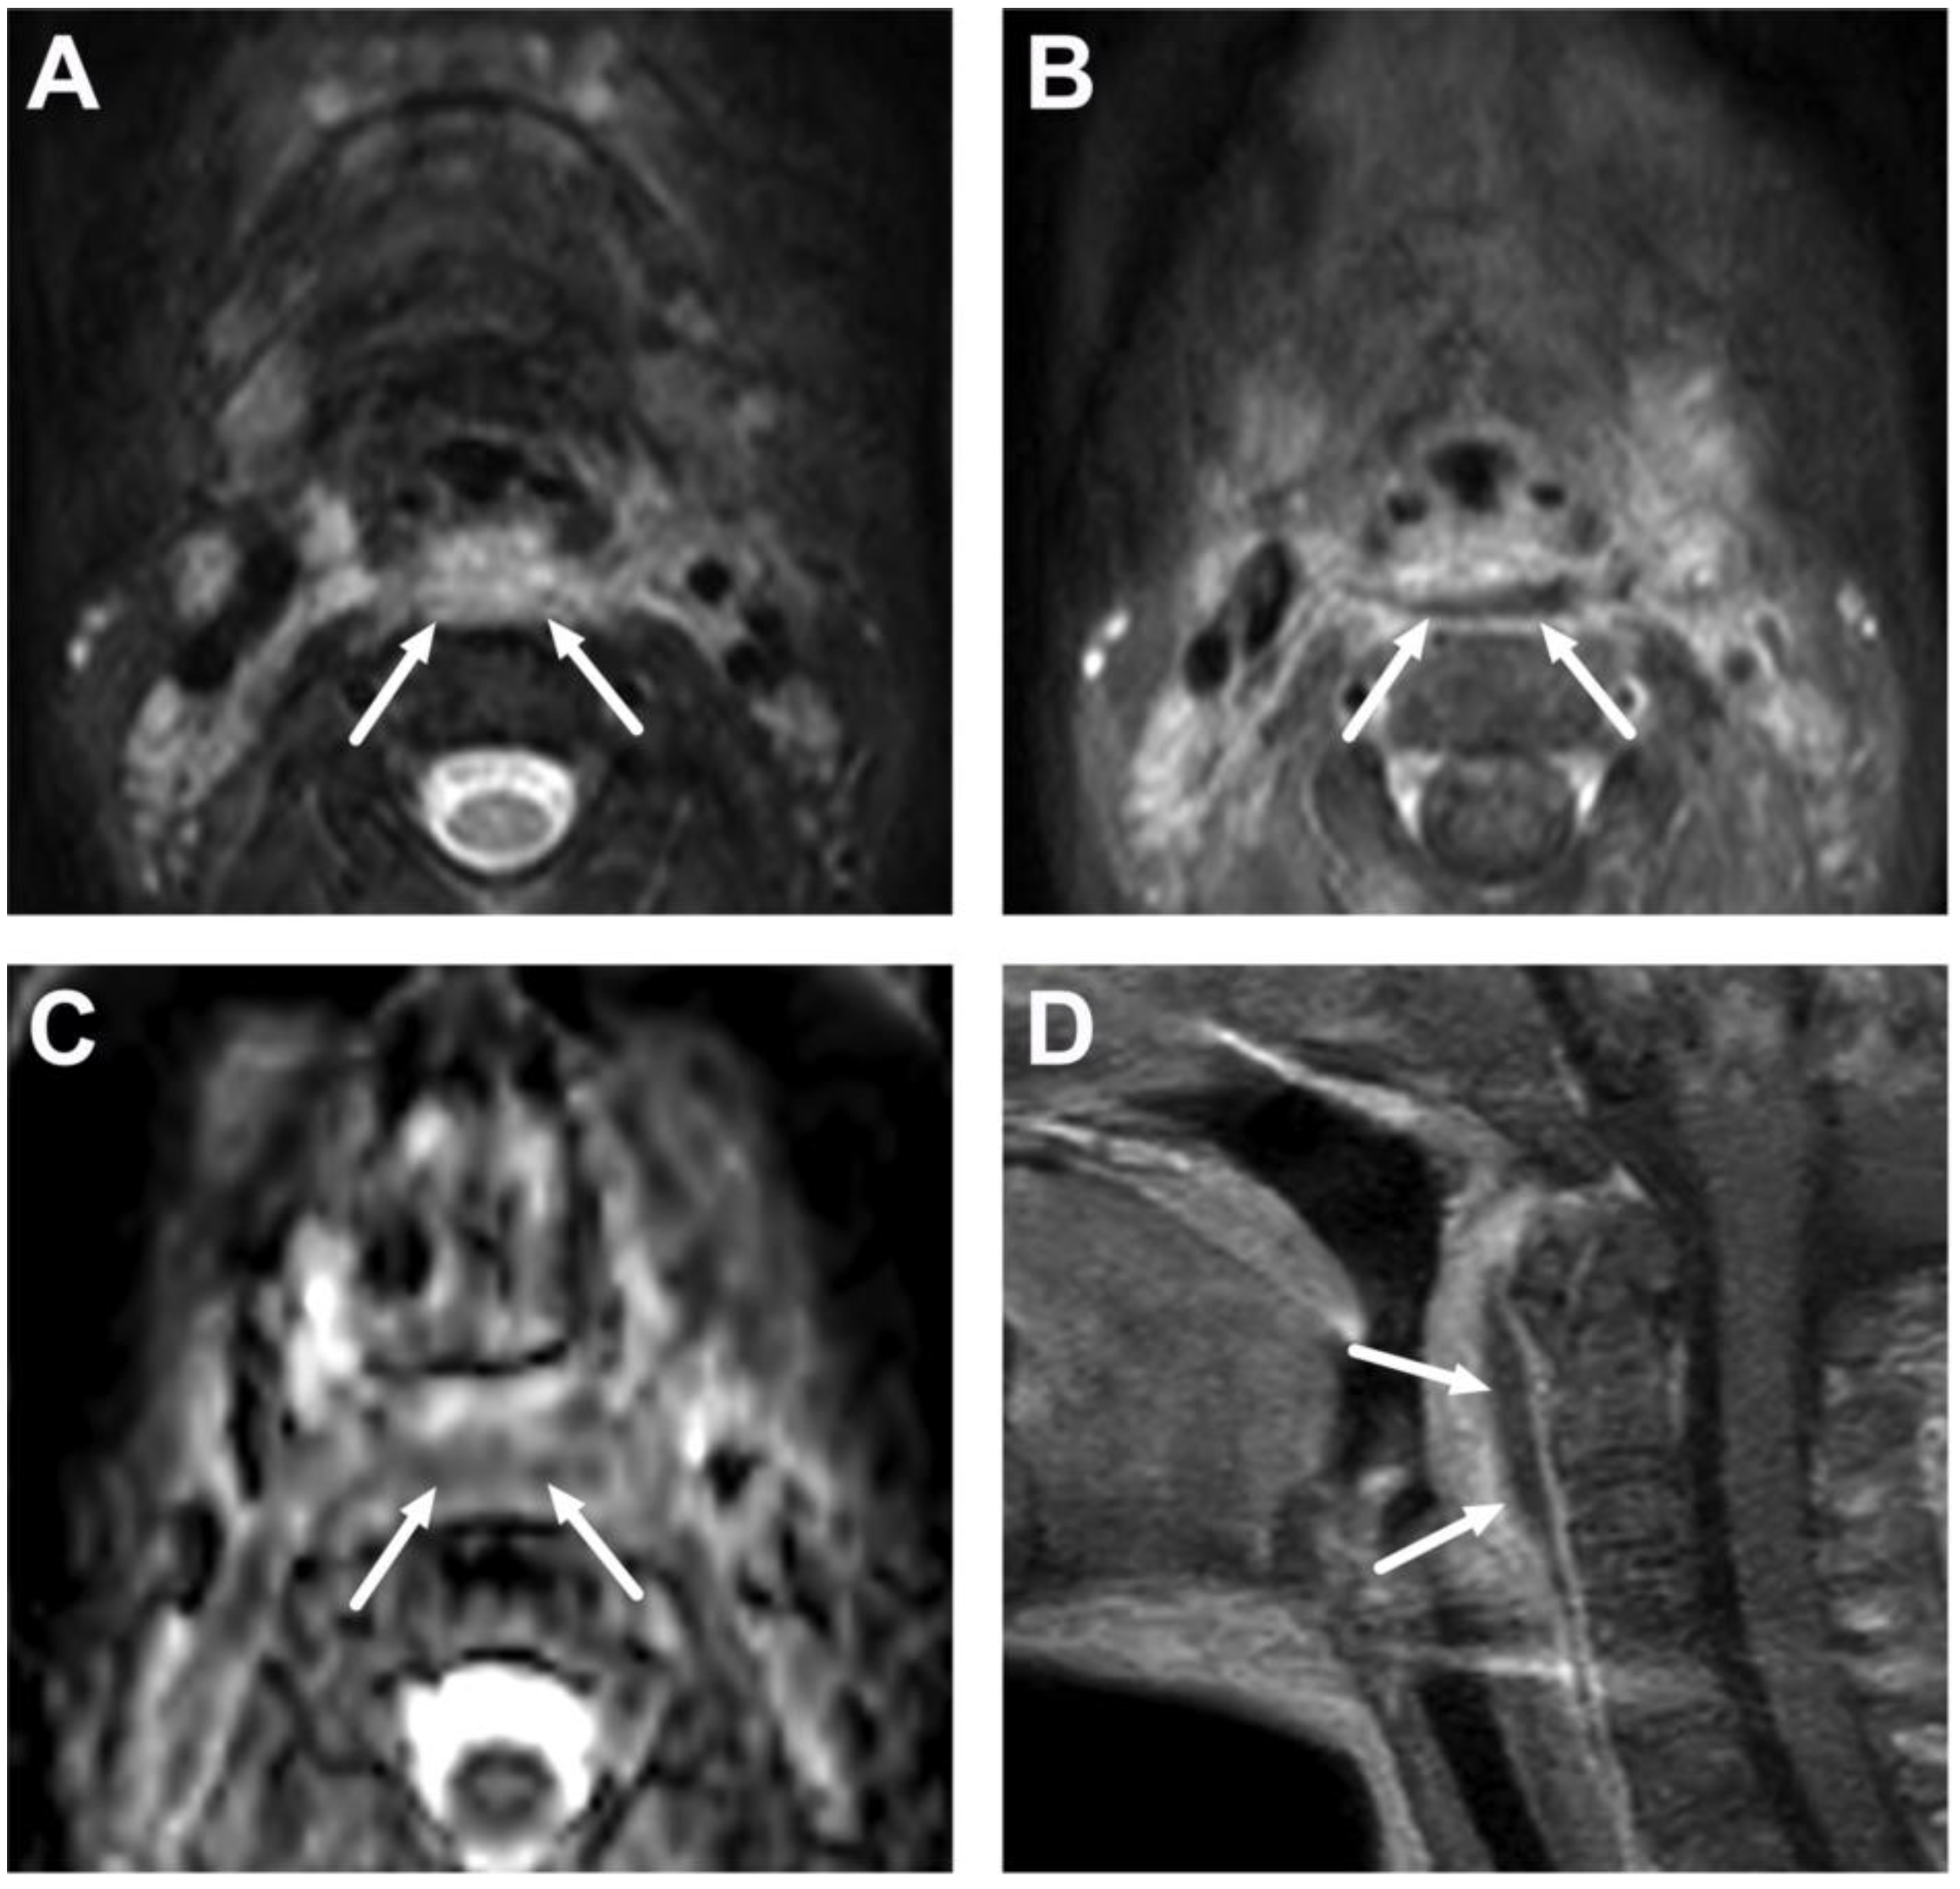

6.1. Mediastinitis

6.2. Venous Thrombosis

| Complications | Whole protocol | Abscess extending to multiple deep neck spaces, mediastinis, venous thrombosis, and airway compromise. | Detection of potentially life-threatening conditions. | Magnetic resonance angiography (MRA) or CECT may be needed to diagnose venous thrombosis; defining airway compromise is difficult. |